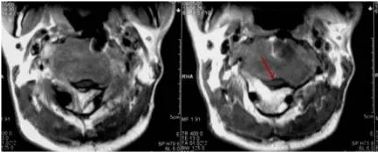

德克萨斯大学MD安德森癌症中心报道,免疫联合治疗缩小了一半以上患者的脑转黑色素瘤。在联合检查点抑制剂ipilimumab和nivolumab的单臂研究中,94名患者最少随访9个月,中位随访时间为14个月,24名(26%)有完全反应,28名(30%)有部分反应和2(2%)名稳定。  由于近年来IV期黑色素瘤的治疗有了很大改善,但是脑转移患者仍然是最需要新疗法